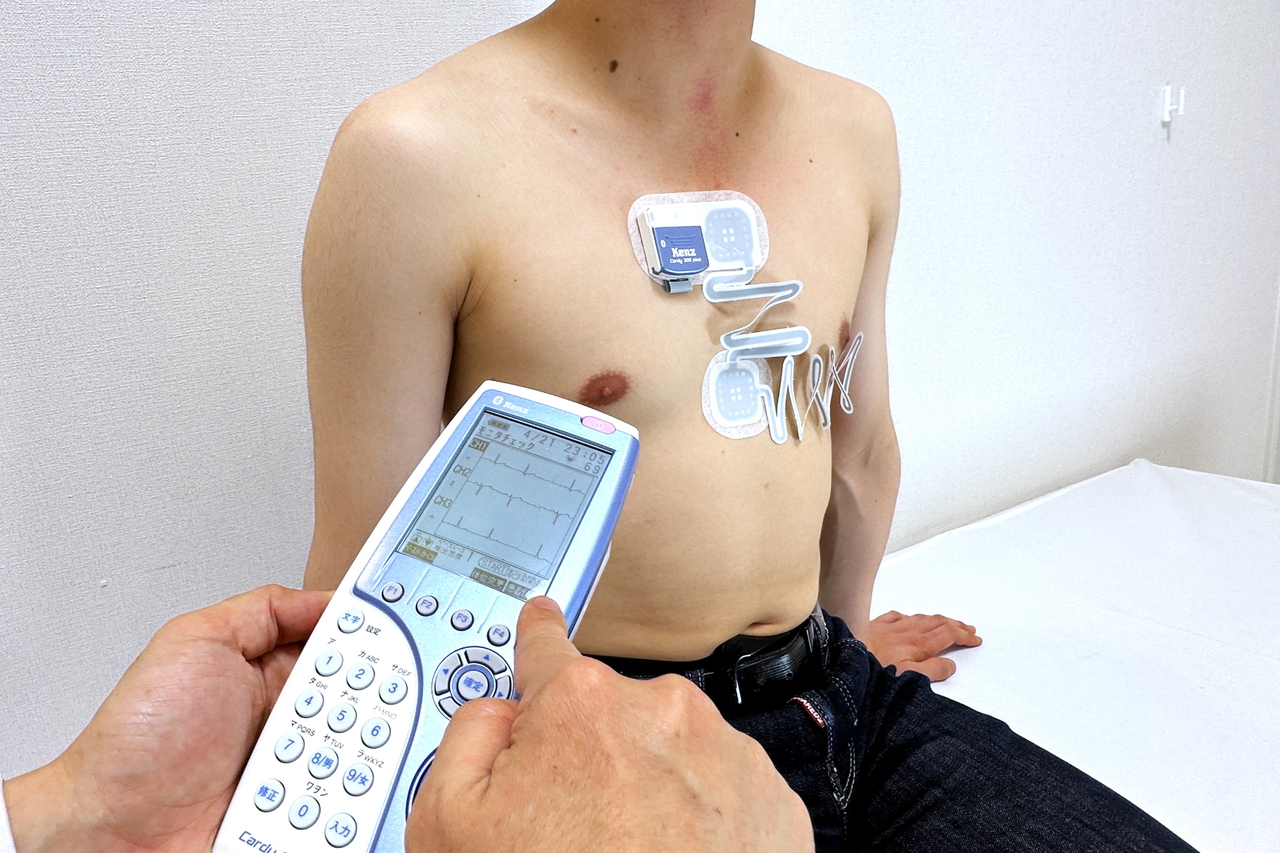

超小型で携帯型の心電計であり、電極を胸部に装着したまま日常生活を送っていただきます。最大48時間の連続で心電図を記録することで、通勤や運動、睡眠時など、いつ起こるかわからない、発作的な狭心症や不整脈の検出が可能であり、循環器科の診療において必須といえる機器です。

当機種は、防塵・防水仕様の最新型であり、装着したままの入浴も可能です。